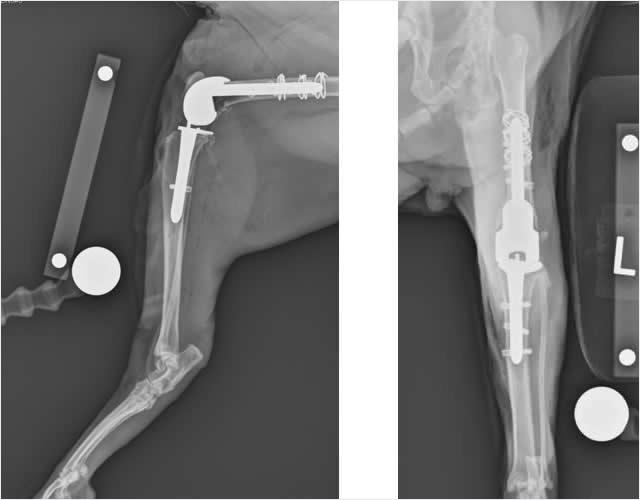

Osteaosarcoma (Bone Cancer)

Possible signs: Lameness and reluctance to put weight on a particular leg; painful hard lump or swelling.The most frequently diagnosed tumor of the bone in both dogs and cats is osteosarcoma, or bone cancer. The clinical signs of any bone tumor include lameness and reluctance to put weight on a particular leg because the tumor makes it painful to walk on. If the tumor occurs in just the right location, you may be able to feel a hard lump or swelling on the bone, although be advised that these lumps can be extremely painful to the touch. An X-ray and biopsy will be necessary to confirm the diagnosis.